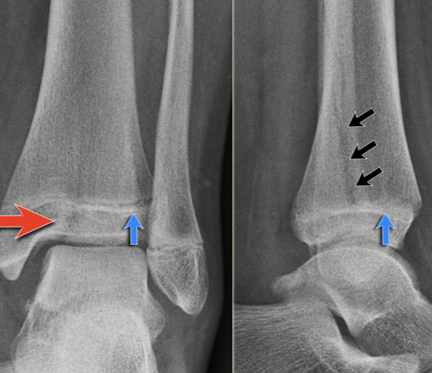

Epiphyseal Injuries

The weakest point of long bones is the cartilage growth plate (epiphyseal plate).

It is a frequent site of damage during trauma.

Injury may affect future bone growth.

Treatment may include open reduction and internal fixation to prevent growth disturbances.

Salter-Harris Fractures

The Salter-Harris Classification system is used to describe fractures involving the epiphyseal growth plate.

These injuries have a higher likelihood of healing difficulties.

The most common concern is:

Growth arrest with the potential for deformity and limb length discrepancy.

Salter-Harris I and II fractures can be treated with closed reduction, casting, or splinting.

Salter-Harris III, IV and V will require surgery—open reduction.

Salter-Harris V fracture diagnosis may be delayed unless there is a high degree of clinical suspicion, and often the diagnosis is not made at the initial presentation.

May see in a follow-up examination as the patient starts to have some healing.